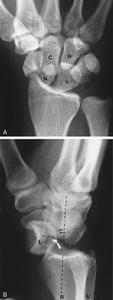

月骨脫位--檢查(1)X線正位片:可見腕骨排列紊亂,頭狀骨與月骨影重疊,舟月間隙增大,舟骨長軸變短,呈皮質環征或舟骨鏇轉,月骨脫位失去四邊形結構,呈三角形影。

(2)X線側位片:出現月骨周圍背側脫位,第3掌骨、頭狀骨與月骨、橈骨失去正常共軸線關係,第3掌骨及頭狀骨的軸線位於月骨及橈骨軸線背側,在此基礎上當月骨向掌側傾斜時,提示為動態性月骨周圍背側脫位,月骨掌側脫位時可見第3掌骨、頭狀骨、橈骨共軸承關係不變,而月骨位於以上諸骨軸線掌側。

月骨周圍脫位線正位片可見腕骨弧線中斷頭狀骨與月骨橈骨與舟骨投影重疊加重,腕中關節間隙消失,舟月骨間關節間隙變寬,月骨周圍腕骨及橈尺骨遠端可有骨折,X線側位片可見舟骨掌屈加大,縱軸與橈骨縱軸近乎垂直,近極位於橈骨遠端關節面背側緣或掌側緣上,月骨與橈骨遠端關係正常,橈月關節間隙無明顯異常,其餘腕骨向背側或掌側脫位其中,頭狀骨最突出。頭由月骨遠側凹面內脫出,位於月骨背側或掌側月骨周圍腕骨如有骨折。其遠側段多脫向背側或掌側,而近側段仍滯留在原位與月骨保持正常關係。

月骨脫位X線正位片可見月骨輪廓,由梯形變為三角形。周圍關節間隙不平行或寬窄不等,側位見月骨掌側脫位輕者,月骨仍位於橈骨遠端凹面內,掌屈過度,橈月關節背側間隙變寬,頭狀骨與月骨背側面相對重者,月骨掌屈大於90°進入腕管內與橈骨遠端、頭狀骨完全分離。月骨周圍脫位與月骨脫位X線片影像雖然顯著,但漏診率至今仍居高不下。恐怕與X線側位片骨影相互重疊,單一腕骨輪廓難於分辨有關。診斷困難者可做CT檢查。

根據X線片檢查不僅可以明確診斷,尚可對脫位類型進行分類。正常時腕關節正位片上月骨呈四方形,位於橈骨與頭狀骨之間,在側位片上頭骨、月骨、橈骨三者呈直線關係排列,上述關係的異常很易在X線上發覺,因此診斷並不困難。